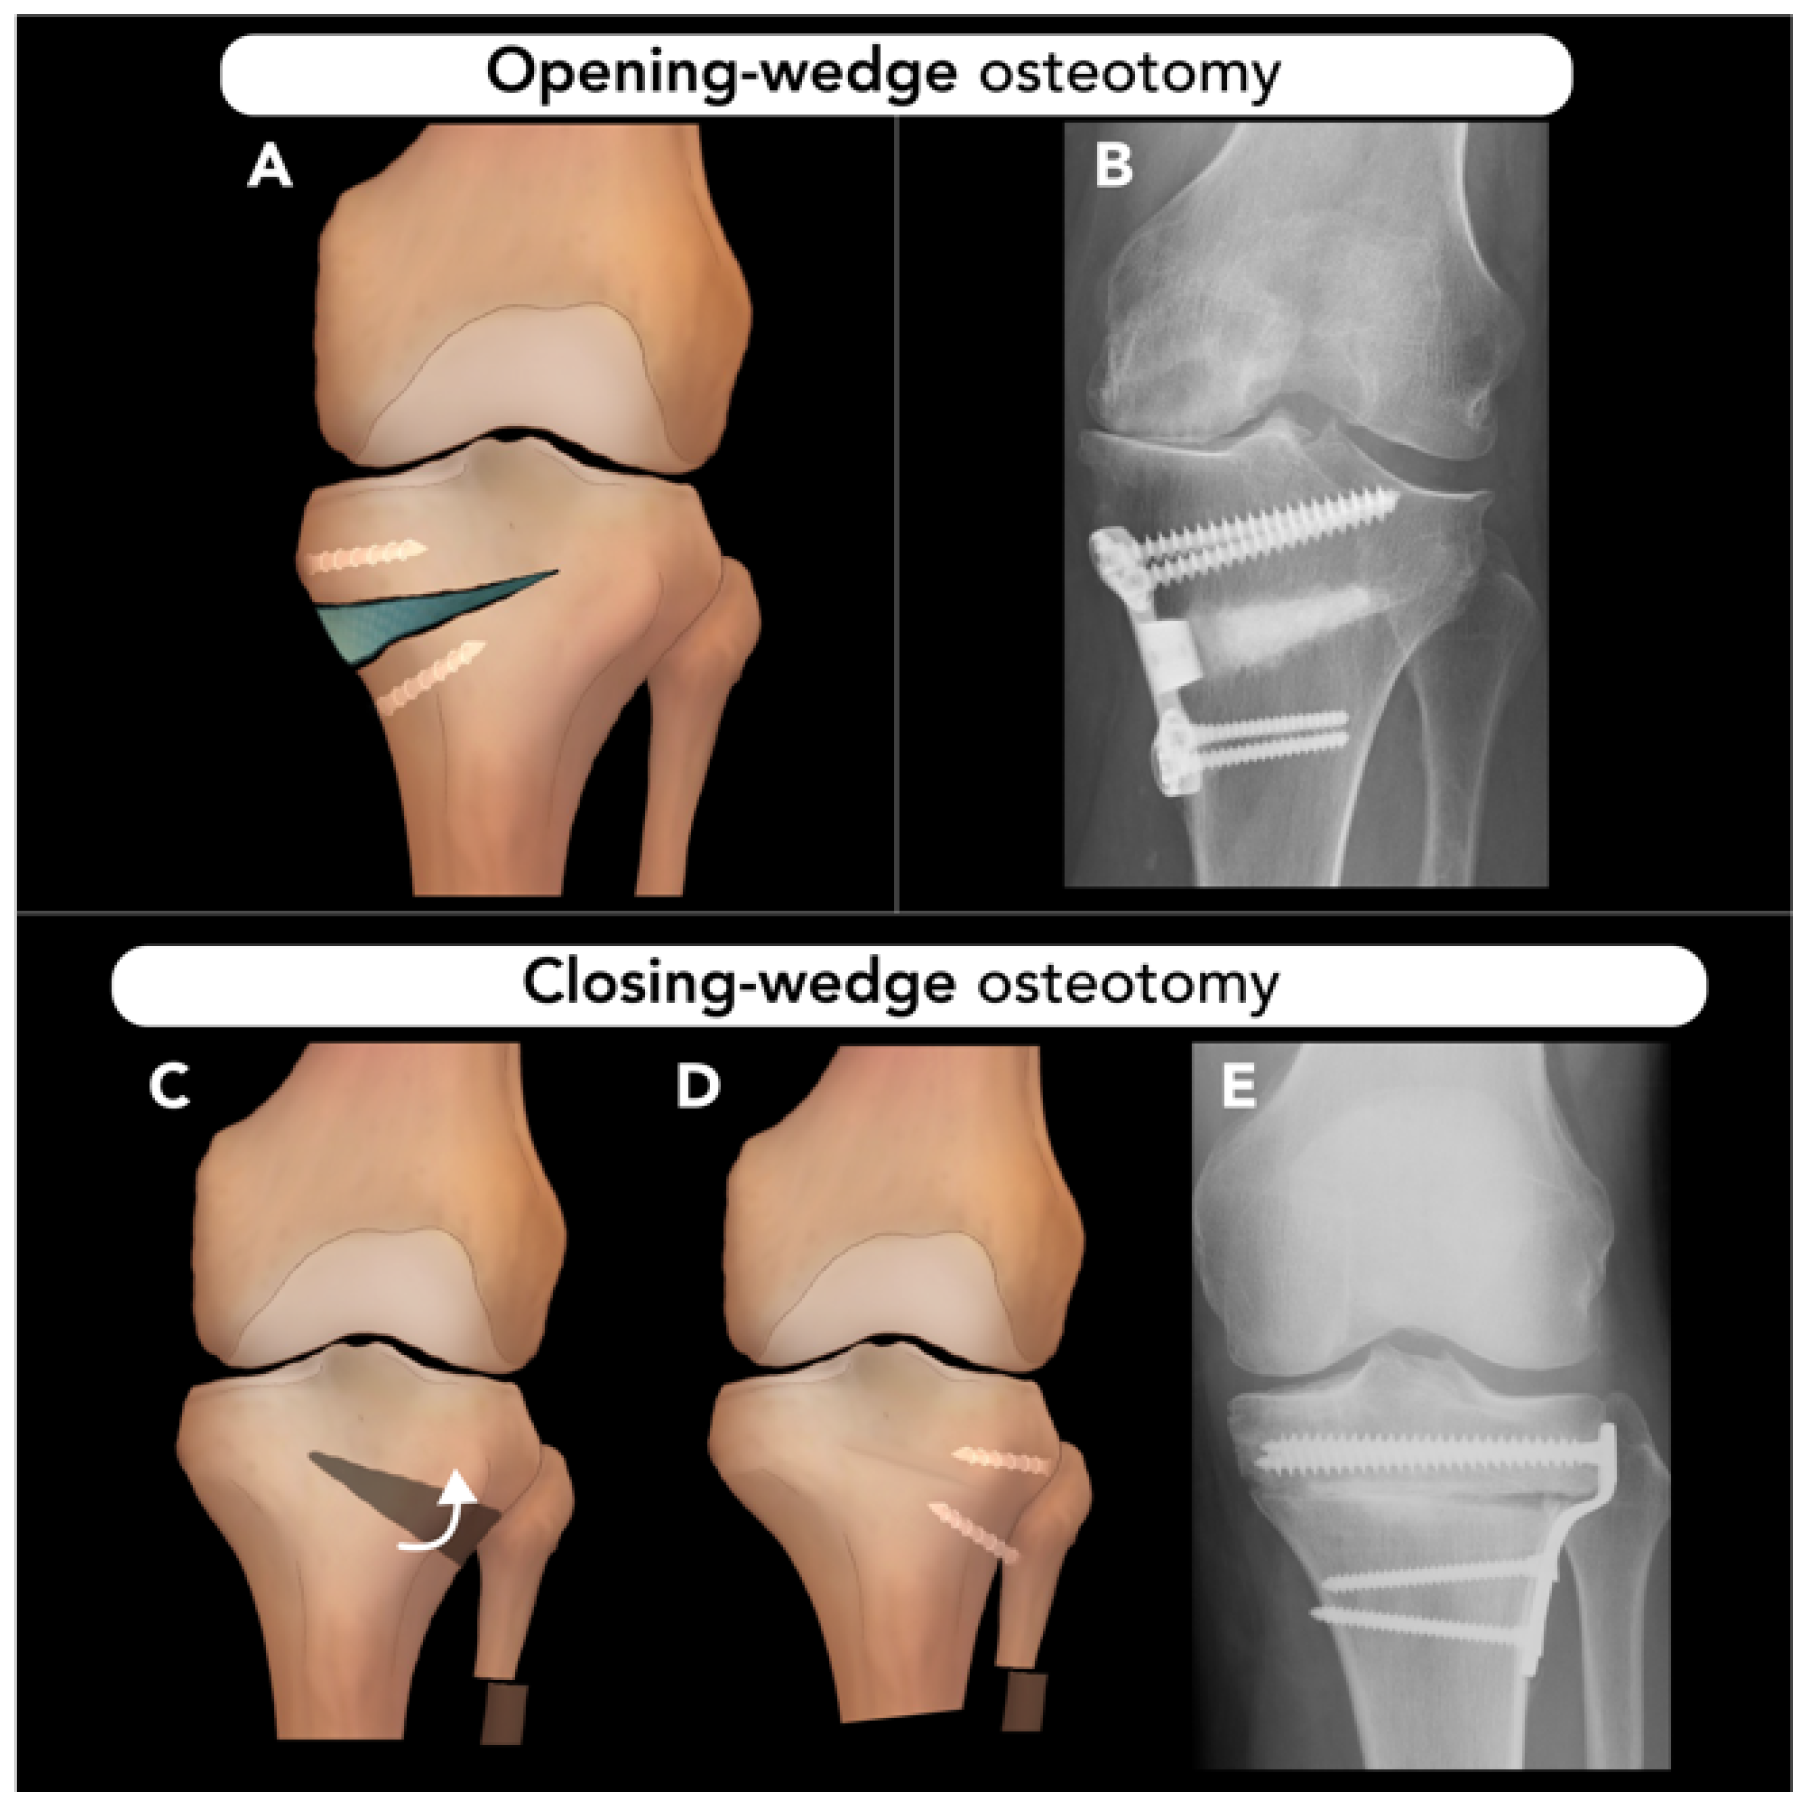

2.3.1. High Tibial Osteotomy